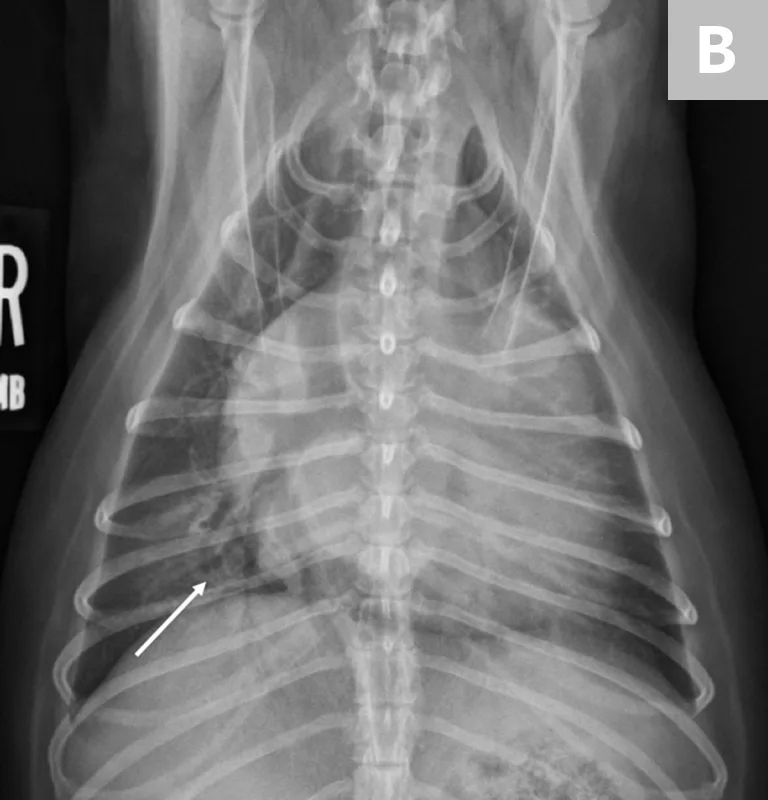

If clinical signs are not immediately life-threatening, at a minimum, a lateral thoracic radiograph should be obtained. Thoracic radiography is the gold standard for diagnosing pulmonary edema and venous congestion secondary to L-CHF.3,5 If the patient is not in distress, a 3-view study with a ventrodorsal or dorsoventral (VD/DV) view and opposite lateral thoracic views is ideal. Characteristic findings of cardiogenic pulmonary edema include increased interstitial-to-alveolar infiltrates of the perihilar and/or caudodorsal lung field in dogs.3,5 (See Figures 1A and 1B.)

FIGURE 1

(A) L-CHF in a Cavalier King Charles spaniel with mitral valve disease. Enlarged cranial lobar vessels are marked by the arrows. Enlarged left atrium is marked with an asterisk. (B) DV projection shows a caudal interstitial-to-alveolar pattern with air bronchograms (arrow). Images courtesy of University of Florida Small Animal Hospital